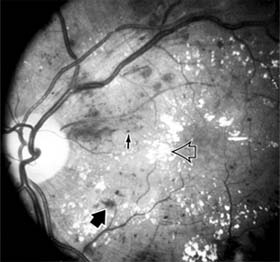

Diabetic retinopathy is a progressive microangiopathy characterized by small vessel damage and occlusion. The earliest pathologic changes are thickening of the capillary endothelial basement membrane and reduction of the number of pericytes. Background diabetic retinopathy is a clinical reflection of the hyperpermeability and incompetence of involved vessels. The capillaries develop tiny dot-like outpouchings called microaneurysms, while the retinal veins become dilated and tortuous (Figure 10-20).

Figure 10-20: Background diabetic retinopathy with abundant macular exudate (open arrow), micro-aneurysms (small arrow), and intraretinal hemorrhage (large arrow).

Multiple hemorrhages may appear throughout different levels of the retina. Flame-shaped hemorrhages are so shaped because of their location within the horizontally oriented nerve fiber layer, while dot and blot hemorrhages are in the deeper retina, where cells and axons are vertically oriented.

Macular edema is the most frequent cause of visual loss among patients with background diabetic retinopathy. The edema is caused primarily by a breakdown of the inner blood-retinal barrier at the level of the retinal capillary endothelium, allowing leakage of fluid and plasma constituents into the surrounding retina. The edema may be focal or diffuse and appears clinically as thickened, cloudy retina with associated microaneurysms and intraretinal exudate. Circinate zones of yellow, lipid-rich exudate may form around clusters of microaneurysms and are most frequently centered in the temporal portion of the macula. While the prevalence of macular edema is 10% in the diabetic population as a whole, there is a dramatic increase in prevalence in eyes with more severe retinopathy.